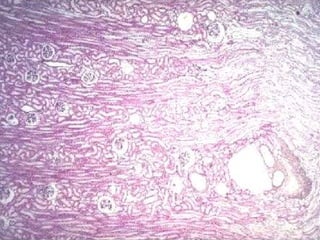

Estructura general del riñón Los riñones (lat.  ren , riñón; gr.  nefros ) son órganos grandes de color rojizo y forma de habichuela que se hallan situados en el retroperitoneo a ambos lados de la columna vertebral.  En el polo superior de cada riñón, incluida dentro de la fascia renal y de una gruesa capa protectora de tejido adiposo perirrenal, hay una  glándula suprarrenal. El borde medial del riñón es cóncavo y posee una incisura vertical denominada  hilio,  que permite la entrada y la salida de los vasos y los nervios renales y contiene el segmento inicial del uréter (dilatado a la manera de un embudo) llamado  pelvis  renal.

A causa de su distribución y sus diferencias de longitud los túbulos de la médula en conjunto forman varias estructuras cónicas llamadas  pirámides renales  o  medulares  (de Malpighi).  Cada pirámide está dividida en una  zona externa  o  médula externa  (contigua a la corteza) y una  zona interna  o  médula interna. La médula externa se subdivide a su vez en una  franja interna  y una  franja externa.

El vértice de cada pirámide, llamado  papila,  se proyecta dentro de un  cáliz menor,  que es una extensión con forma de copa de la pelvis renal. La punta de la papila, también conocida como  área cribosa  o  cribiforme (lat. cribrum, colador),  está perforada por los orificios de desembocadura de los conductos colectores .

La nefrona o nefrón La nefrona o nefrón es la unidad estructural y funcional fundamental del riñón y en cada riñón humano hay alrededor de 2 millones de ellas. La nefrona consiste en el corpúsculo renal y un sistema de túbulos.

El  corpúsculo renal  constituye el comienzo de la nefrona y está compuesto por un  glomérulo,  que es un ovillo capilar formado por 10 a 20 asas capilares, rodeado por una estructura epitelial bilaminar caliciforme llamada  cápsula renal  o  cápsula de Bowman.  Los capilares glomerulares reciben la sangre desde una  arteriola aferente  y  la envían a una  arteriola eferente  que luego se ramifica para formar una red capilar nueva que irriga los túbulos renales.

Partes tubulares de la nefrona Segmento grueso proximal,  compuesto por el  túbulo contorneado proximal  (pars  convoluta)  y el  túbulo recto proximal  (pars  recta). Segmento delgado,  que forma la parte delgada del asa de Henle. Segmento grueso distal,  compuesto por el  túbulo recto distal  (pars  recta)  y el  túbulo contorneado distal  (pars  convoluta).

Túbulos y conductos colectores Los túbulos colectores comienzan en el laberinto cortical en la forma de  túbulos de conexión  o de  túbulos colectores arciformes  y siguen hasta el rayo medular, donde se unen a los  conductos colectores. La región de la papila que contiene los orificios de desembocadura de estos conductos colectores se conoce como  área cribosa o cribiforme.